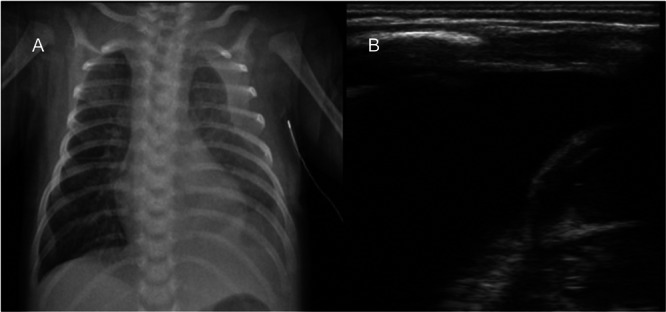

Results: Thirty-five newborns (15 females, 20 males) were diagnosed with chylothorax, 11 congenital and 24 acquired (18 CDH, 5 esophageal atresia, 1 caval thrombosis). After first-line treatment, 7 (20%) were good responders, 19 (54%) were partial responders, and 9 (26%) were non-responders. Non-responders received iodopovidone pleurodesis, which resolved the condition in all cases (median time to resolution was 4 days). Complications during hospitalization included 8 cases of sepsis (1 fatal), 5 of atelectasis (4 related to pleurodesis), and 4 venous thromboses. Partial responders had significantly more sepsis (p = 0.029) but less atelectasis (p = 0.025) compared to non-responders, with similar resolution times and hospital stays. After a median follow-up of 3 years, there were no recurrences or thyroid dysfunction in the iodopovidone group.